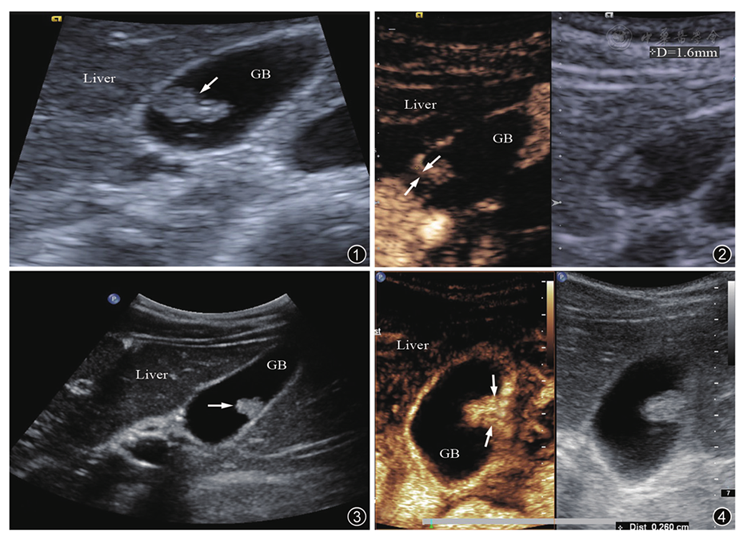

图1~4 肿瘤性息肉与非肿瘤性息肉造影图像基底部宽度。图1 常规超声所示胆囊壁等回声结节(箭头所示),结节最大直径1.1 cm;图2 超声造影动脉期结节基底部较窄(箭头所示),宽度约1.6 mm,手术病理证实为胆固醇息肉;图3 常规超声所示胆囊壁高回声结节(箭头所示),结节最大直径1.1 cm;图4 超声造影动脉期结节基底部较宽(箭头所示),手术病理证实为胆囊腺瘤